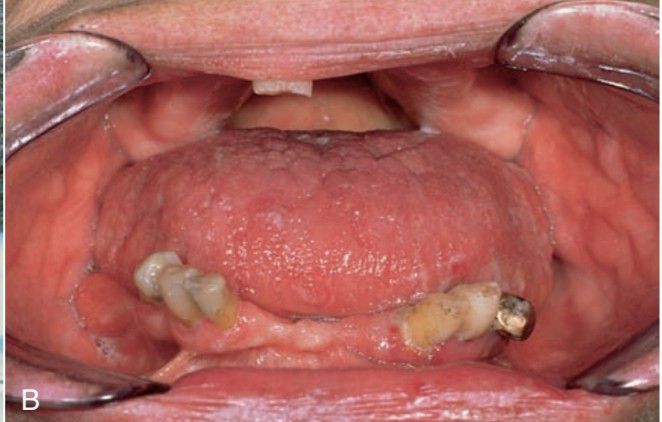

Acromegaly

Acromegaly of jaws